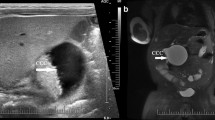

Notably, hepatoblastoma was identified at 46 days of age in patient #17, at 218 days in patient #18, and at 13 months of age in patient #8 of UPD-group (Figure 4). It was surgically removed in patients #8 and #18, although chemotherapy was not performed because of poor body condition. In patient #17, neither an operation nor chemotherapy could be carried out because of the patient’s severely poor body condition. Histological examination of the removed tumors revealed a poorly differentiated embryonal hepatoblastoma with focal macrotrabecular lesions in patient #8 (Figure 4) and a well-differentiated hepatoblastoma in patient #18.10

Hepatoblastoma in patient #8 of UPD-group. (a) Macroscopic appearance of the hepatoblastoma with a diameter of ~8 cm. (b) Microscopic appearance of the hepatoblastoma exhibiting a trabecular pattern. The hepatoblastoma cells are associated with eosinophilic cytoplasm and large nuclei, and resemble fetal hepatocytes.